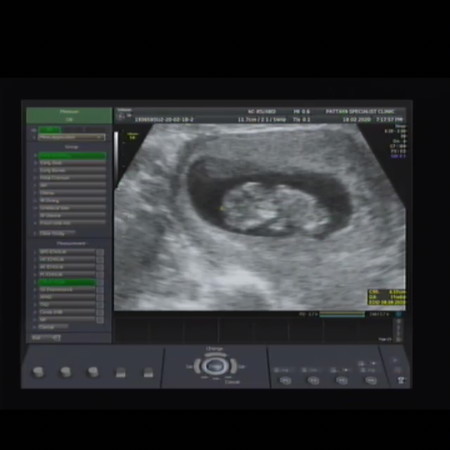

ฝากที่ อนามัย หมอนับตามประจำเดือน ตอนนี้ได้13สัปดา4วัน. แต่ไปอันตร้าซาว หมอนับ11สัปดา. อันไหนแม่งกว่าค่ะ. รูปอันตร้าซาว น้องไม่หงายท้อง เหมือนคนอื่น ปกติรึเปล่าค่ะ พอดีหมอไม่บอกรายละเอียดอะไรเลยคะ